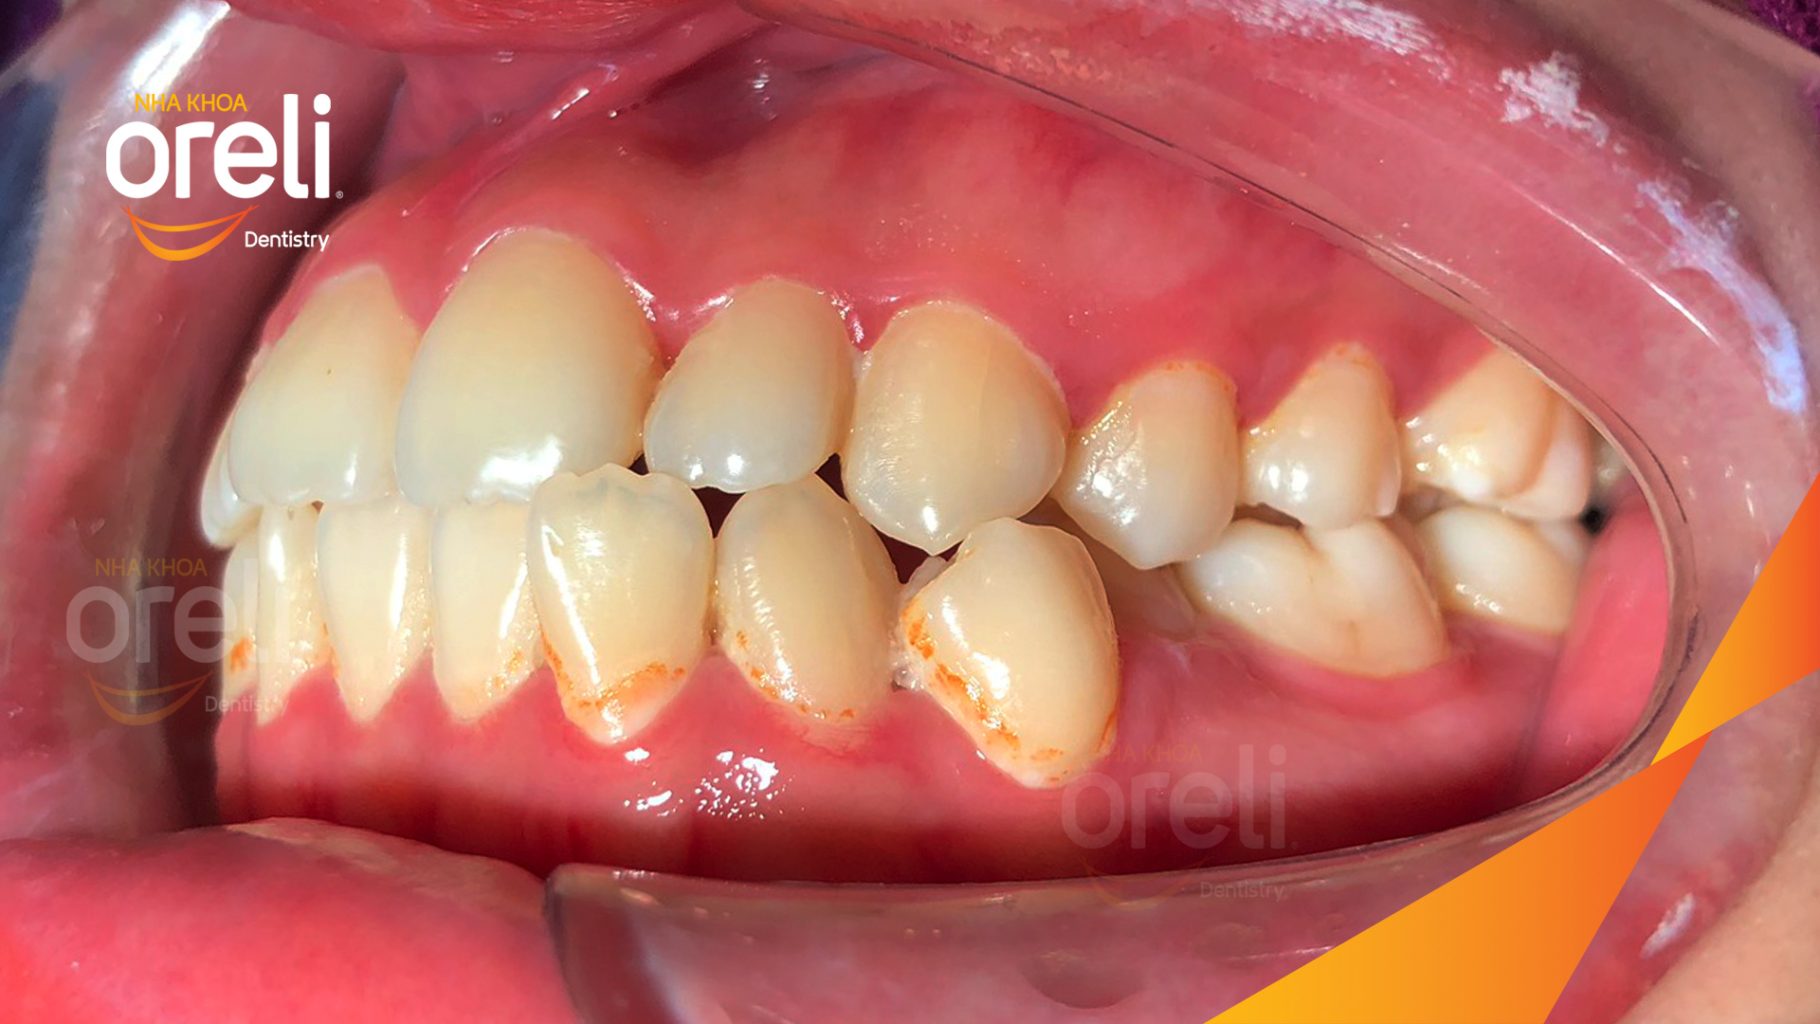

Hành trình thay đổi nụ cười ca lệch khớp cắn hạng 3, hàm dưới trượt ra trước và nhô xương hai hàm.

Hình ảnh thực tế